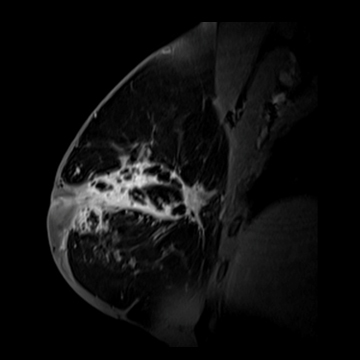

乳腺

MRI画像(提供:シーメンスジャパン株式会社)